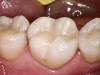

After a clean and neat cavity preparation, liner was placed on the deep cavity surface to mask the dark amalgam stain. The liner was light-cured for 20 seconds. A wide bevel was placed on the occlusal surface, and then a ring and matrix were placed. A selective enamel etching was performed with 37% phosphoric acid (Figure 3), rinsed, and dried. Universal bond was prepared by adding one drop from each bottle of the adhesive product into a mixing well and then briefly mixing. The bond was then placed (Figure 4) and air-dried with low air for 5 seconds, then with stronger air for another 5 seconds. No light-curing was needed for this bonding system. Then, one-shade composite was placed in small increments using a condenser. Before light-curing, some occlusal anatomy was created using hand instruments, including an acorn-shaped burnisher (Figure 5) and blue titanium CIB3. The occlusal adjustments and more detailed anatomy were created using a football-shaped diamond bur and a needle-shaped diamond bur. The final finishing and polishing were done using a large, coarse disc, a fine-needle diamond bur, and white Arkansas stone. A postoperative photograph (Figure 6) showed how the restoration blended naturally with the tooth. Figure 7 and Figure 8 feature a bitewing x-ray and photograph of the tooth taken during the 6-month recall examination.

This Class II restoration demonstrated the versatility and ease of use provided by universal bonding agents. These bonding agents, such as the one used in this case, provide an all-in-one bond system that does not require light-curing, surface agitation, or a post-placement wait period.5 Universal bonding agents save time when multiple restorations in quadrant dentistry are performed. Additional activators and primers were not needed, reducing inventory cost and chairtime compared with using a non-universal bonding agent.5 A final benefit involves the reduced risk of failure in cases such as deep Class II restorations and post-and-core buildups that are difficult to reach and fully cure with light-curing.11 These agents also offer high bond strength and no postoperative sensitivity.